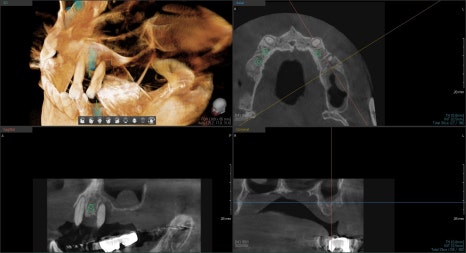

현재 뼈 상태에 맞게 위치와 개수를 정하여 수술을 끝낸 사진입니다.

어금니의 기준점이 없어져 엑스레이의 상이 왜곡되어 나타나 보이지만

의도된 위치에 잘 식립이 되어있음을 확인했습니다.

원하는 임플란트의 고정값을 얻은 후 최종 보철이 완성되었습니다.

과거에 얇았던 잔존골이 노란색으로 표시된 것처럼 두껍게 뼈가 형성된 것을 볼 수 있습니다.